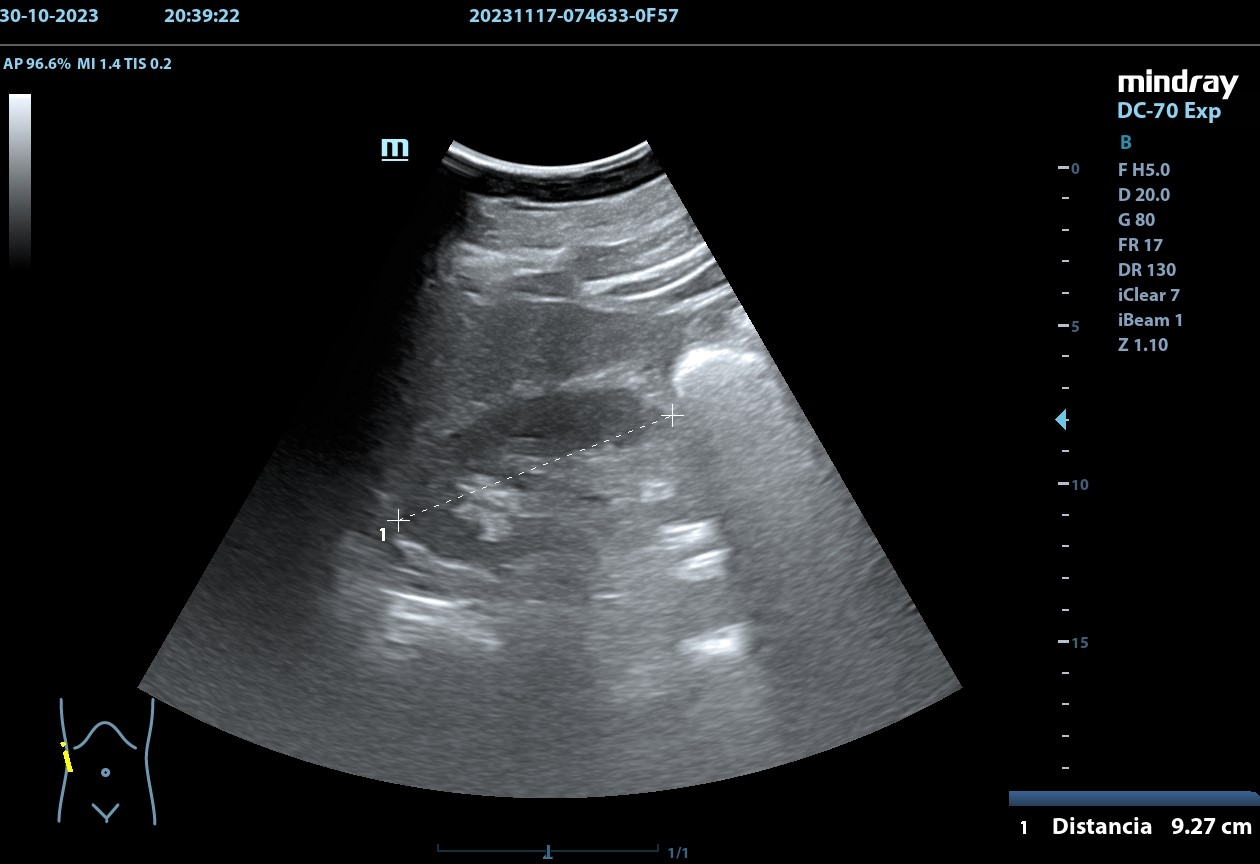

Se realiza, en consulta, una ecografía de las vías urinarias (POCUS), apreciando una lesión excrecente, pediculada, de 7,48 x 6,14 cm, que afecta a la pared izquierda y superior de la vejiga. Doppler negativo. No apreciándose jets ureterales. Riñón izquierdo de 11cm, y derecho de 9.27 cm, sin signos de dilatación de las pelvis renales que sugieran hidronefrosis.